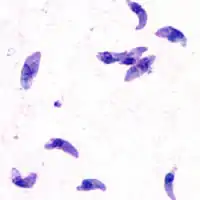

| T. gondii tachyzoites | |

Acute toxoplasmosis is often asymptomatic in healthy adults.[13][14] However, symptoms may manifest and are often influenza-like: swollen lymph nodes, headaches, fever, and fatigue,[15] or muscle aches and pains that last for a month or more. It is rare for a human with a fully functioning immune system to develop severe symptoms following infection. People with weakened immune systems are likely to experience headache, confusion, poor coordination, seizures, lung problems that may resemble tuberculosis or Pneumocystis jirovecii pneumonia (a common opportunistic infection that occurs in people with AIDS), or chorioretinitis caused by severe inflammation of the retina (ocular toxoplasmosis).[15] Young children and immunocompromised people, such as those with HIV/AIDS, those taking certain types of chemotherapy, or those who have recently received an organ transplant, may develop severe toxoplasmosis. This can cause damage to the brain (encephalitis) or the eyes (necrotizing retinochoroiditis).[16] Infants infected via placental transmission may be born with either of these problems, or with nasal malformations, although these complications are rare in newborns. The toxoplasmic trophozoites causing acute toxoplasmosis are referred to as tachyzoites, and are typically found in various tissues and body fluids, but rarely in blood or cerebrospinal fluid.[17]

While rare, skin lesions may occur in the acquired form of the disease, including roseola and erythema multiforme-like eruptions, prurigo-like nodules, urticaria, and maculopapular lesions. Newborns may have punctate macules, ecchymoses, or "blueberry muffin" lesions. Diagnosis of cutaneous toxoplasmosis is based on the tachyzoite form of T. gondii being found in the epidermis.[30] It is found in all levels of the epidermis, is about 6 by 2 μm and bow-shaped, with the nucleus being one-third of its size. It can be identified by electron microscopy or by Giemsa staining tissue where the cytoplasm shows blue, the nucleus red.[31]

In its lifecycle, T. gondii adopts several forms.[32] Tachyzoites are responsible for acute infection; they divide rapidly and spread through the tissues of the body. Tachyzoites are also known as "tachyzoic merozoites", a descriptive term that conveys more precisely the parasitological nature of this stage.[33] After proliferating, tachyzoites convert into bradyzoites, which are inside latent intracellular tissue cysts that form mainly in the muscles and brain. The formation of cysts is in part triggered by the pressure of the host immune system.[34] The bradyzoites (also called "bradyzoic merozoites") are not responsive to antibiotics. Bradyzoites, once formed, can remain in the tissues for the lifespan of the host. In a healthy host, if some bradyzoites convert back into active tachyzoites, the immune system will quickly destroy them. However, in immunocompromised individuals, or in fetuses, which lack a developed immune system, the tachyzoites can run rampant and cause significant neurological damage.[32]